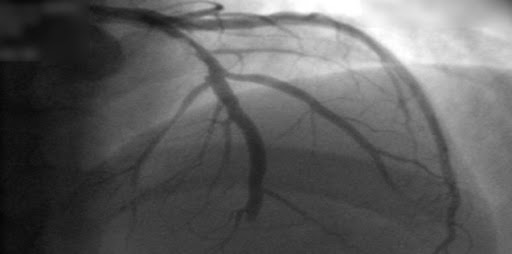

Evaluación con tomografía computada en pacientes con probabilidad intermedia de enfermedad coronaria derivados para angiografía

Sólo el 14% de los evaluados inicialmente con TC requirió angiografía coronaria invasiva; no hubo diferencias clínicas en el seguimiento a 3 años. BMJ, 24 de octubre de 2016